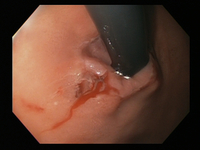

Mallory Weiss tear after application of through-the-scope clip results in haemostasis

From the personal collection of Douglas Adler; used with permission